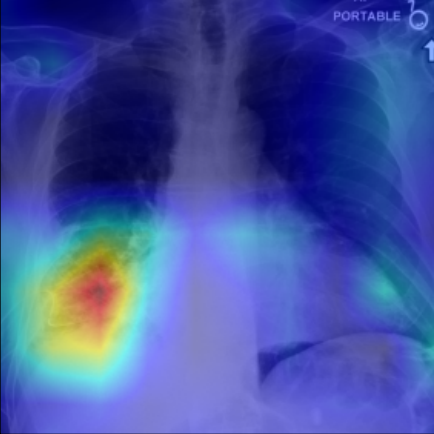

Refer to caption

Figure 5: Visualization of attention map in PLAN on MS-CXR. The red boxes indicate the corresponding ground truth of grounding. Highlighted pixels represent higher activation weights correlating specific words with regions in the image.

IV-B1 Phrase Grounding

Phrase grounding associates textual phrases (e.g., disease descriptions or anatomical terms) with corresponding regions in medical images, offering precise diagnostic insights and enhancing model interpretability. Table II presents the phrase grounding results on the MS-CXR dataset. Using the Contrast-to-Noise Ratio (CNR) [27] as the evaluation metric, PLAN achieved the highest CNR across eight disease categories, outperforming MGCA and PRIOR. Heatmaps generated with Grad-CAM (Figure 4) further illustrate PLAN’s ability to accurately localize lesion sites and align disease-related phrases with image regions. Additional comparisons with baseline methods can be found in Figure 5. These findings highlight PLAN’s superior precision and interpretability in phrase grounding tasks.